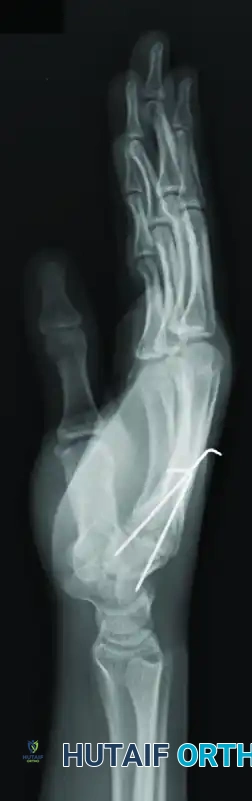

FIGURE 67-29 A-C: Preoperative radiographs of a small finger carpometacarpal fracture-subluxation in a 34-year-old man, demonstrating dorsal displacement and articular incongruity.

FIGURE 67-29 D-F: Postoperative radiographs showing the ring and small finger carpometacarpal joints reduced closed and stabilized with two 0.045-inch Kirschner wires.